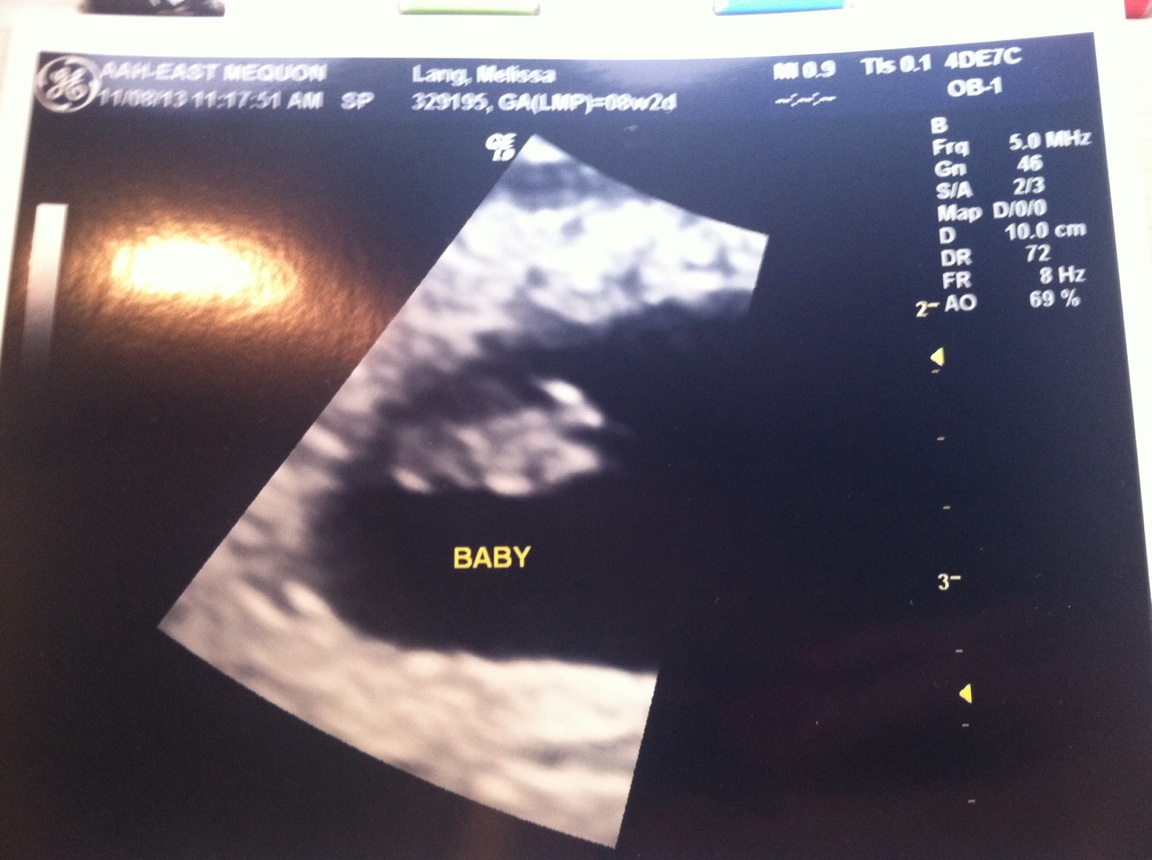

Here are the pics…

Here’s a shot of the little one’s lady parts from underneath. Notice the two legs, tush and three little labia reflection lines.

My favorite little face pic. She’s just so precious with her little hand up by her face. I can’t wait to kiss that little face.

The sweet baby showing her tush just like her puppy brother did later that afternoon. They’re going to be best friends!